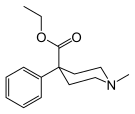

Phenylpiperidines

- Pethidine (meperidine)

The first fully synthetic opioid was meperidine (later demerol), found serendipitously by German chemist Otto Eisleb (or Eislib) at IG Farben in 1932.[228] Meperidine was the first opiate to have a structure unrelated to morphine, but with opiate-like properties.[199] Its analgesic effects were discovered by Otto Schaumann in 1939.[228] Gustav Ehrhart and Max Bockmühl, also at IG Farben, built on the work of Eisleb and Schaumann. They developed "Hoechst 10820" (later methadone) around 1937.[230] In 1959 the Belgian physician Paul Janssen developed fentanyl, a synthetic drug with 30 to 50 times the potency of heroin.[211][231] Nearly 150 synthetic opioids are now known.[228]